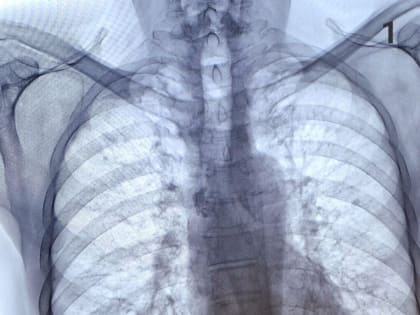

Врач-рентгенолог из Челнов сравнил снимки легких курящего и некурящего человека

Врач-рентгенолог поликлиники №5 Челнов Рамзиль Гильметдинов рассказал, чем отличаются снимки рентгенографа курящего и некурящего человека.